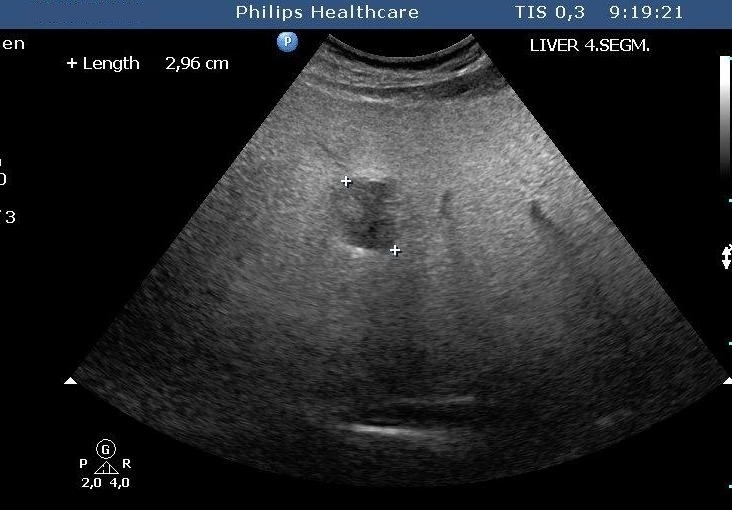

MRI is only needed in case of "atypical" hemangiomas, since ultrasound is the best imaging method for diagnosing the hemangioma. If the ultrasound finding is uncertain, dynamic CT (Figure 19, 20), afterwards nuclear imaging and biopsy are the appropriate choices.

Figure 19: Hemangioma in the liver, native CT

Figure 20: Hemangioma in the liver, contrast enhanced CT

Paraarterial or subcapsular localisation, central thrombosis or fibrosis may interfere with the safety of diagnostic evaluation. In this case, MRI can be performed which is very sensitive to hemangiomas (size under 0,5 cm is also indicated – figure 21).